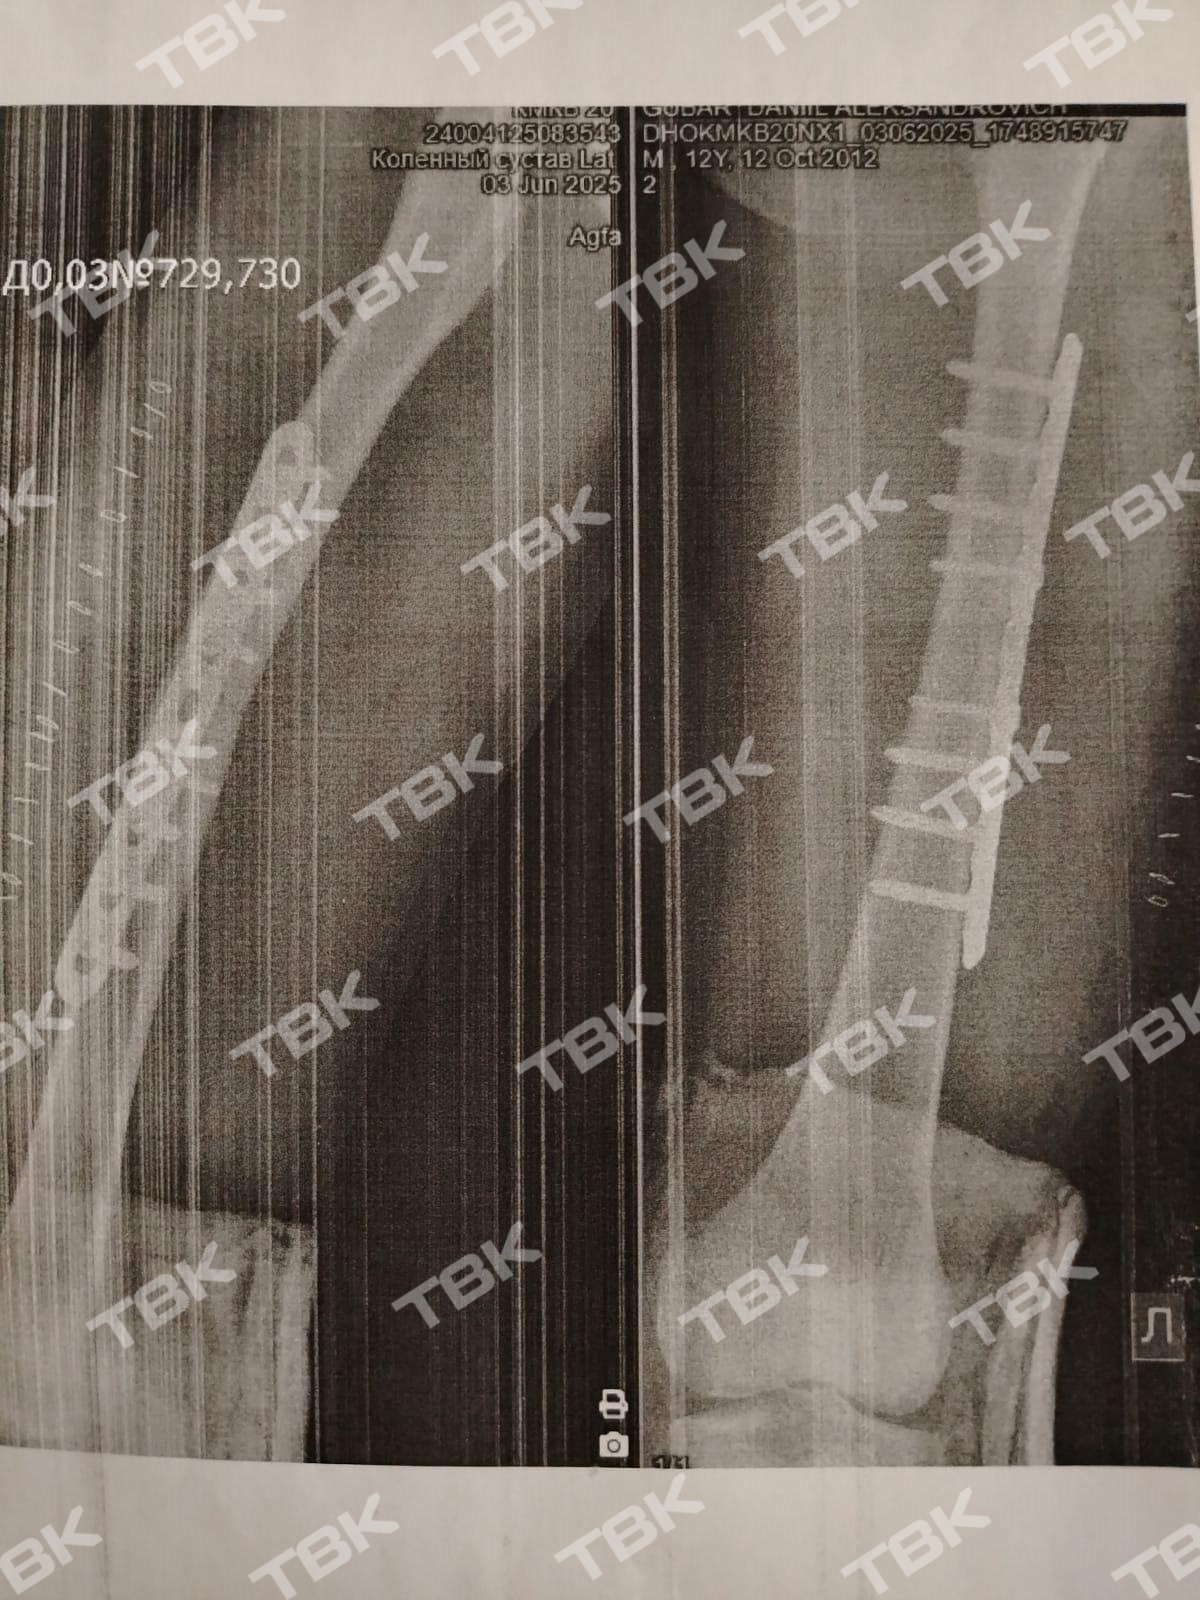

Открытый перелом голени, перелом бедра со смещением и разорванная нога. Так для 12-летнего Даниила закончилась тренировка на лыжероллерной трассе в Зеленогорске. Из леса на трек вылетел 15-летний подросток на питбайке. Очевидцы утверждают, что мотоциклист сбил спортсмена и уехал с места. Теперь Даниил проведет почти полгода со спицами и металлическими болтами в костях. В полиции же отказали в возбуждении и административного и уголовного дела. Как правоохранители это объясняют?

У мальчика обнаружили открытый перелом обеих костей левой голени со смещением, закрытый перелом бедра со смещением, обширную рваную рану на правом бедре и ушиб нижней челюсти.

После госпитализации Даниила перевезли из Зеленогорска в Красноярск, где ему провели операцию. Сейчас в голени 12-летнего мальчика спицы, а на кости бедра – металлическая конструкция. Ногу ребенку собирали буквально по частям, делится мама пострадавшего Надежда.«Даня бы его смог объехать, если бы мотоциклист действительно стоял. Даниил – спортсмен разрядник, имеющий огромный опыт за плечами, уже больше трех лет он занимается. Он работал и на более крутых лыжероллерных трассах – в Бородино и Красноярске спуски гораздо опаснее. Он владеет техникой абсолютно. Мотоциклист двигался – это железобетонно. Он просто двигался на большой скорости и сбил лыжероллера, был встречный удар», – объяснил тренер Вадим Токарев.

Даниилу сейчас нельзя ходить. Конструкцию на бедре не снимут до декабря. Как сказано в постановлении МВД, в возбуждении административного и уголовного дела в отделении зеленогорской полиции матери Даниила отказали: